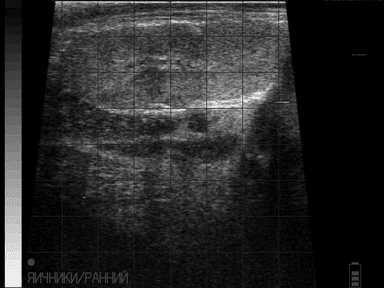

Итак, сегодня предлагаю к обсуждению такую проблему как кистозная дегенерация фолликулов яичника, в простонародье - кисты.

По обычной классификации мы знаем, что есть фолликулярные кисты и лютеиновые кисты (кисты 1 типа и 2 типа).

Предлагаю рассмотреть снимки и в комментариях ответить, какие кисты вы видите и кисты ли это, а потом будем разбираться с каждым случаем в отдельности!